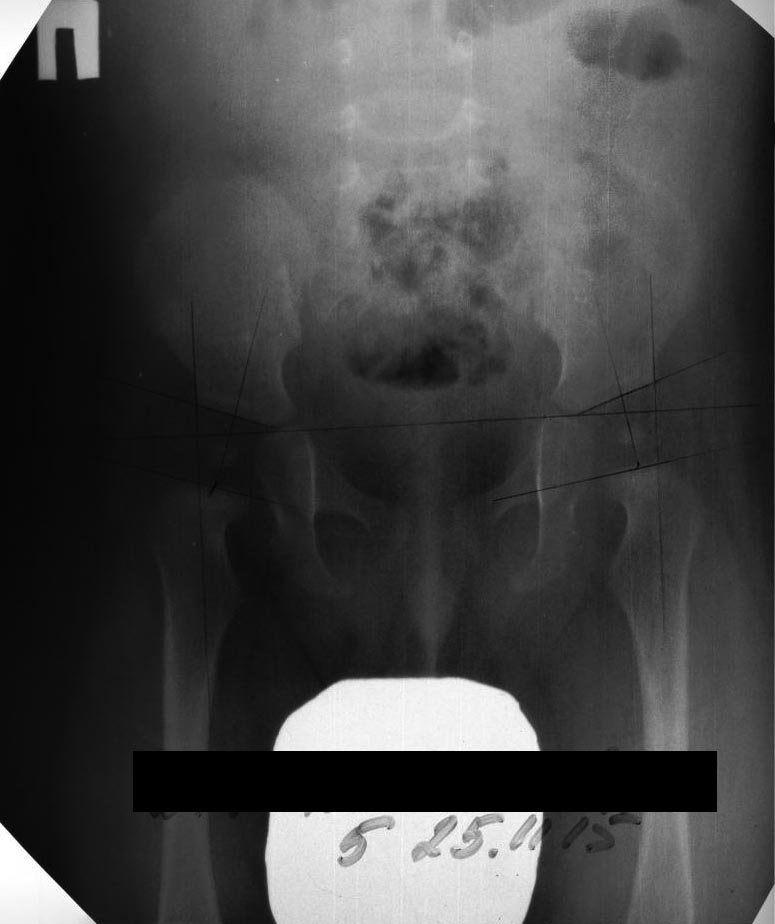

Сообщение с аналогичной темой я отправила ранее. Здесь отправляю снимок ТБС от 2015 года для сравнения и картины в динамике